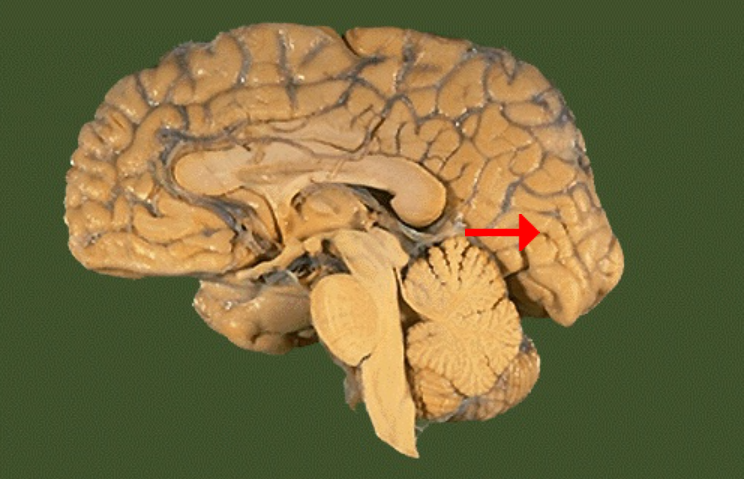

Label this brain part

Thalamus

Label this brain part

Midbrain

Label this brain part

Fourth ventricle

Label this brain part

Medulla